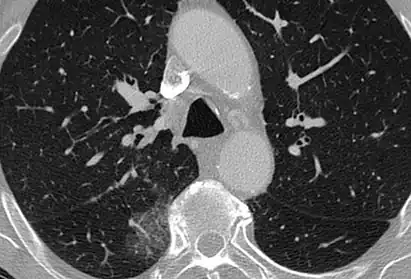

Diffuse

The diffuse pattern typically refers to GGOs in multiple lobes of one or both lungs. Broadly, a diffuse pattern of GGO can be caused by displacement of air with fluid, inflammatory debris, or fibrosis. Cardiogenic pulmonary edema and ARDS are common causes of a fluid-filled lung. Diffuse alveolar hemorrhage is a rarer cause of diffuse GGO seen in some types of vasculitis, autoimmune conditions, and bleeding disorders.[6]

Inflammation and fibrosis can also cause diffuse GGOs. Pneumocystis pneumonia, an infection typically seen in immunocompromised (e.g. patients with AIDS) or immunosuppressed individuals, is a classic cause of diffuse GGOs. Many viral pneumonias and idiopathic interstitial pneumonias can also lead to a diffuse GGO pattern. Radiation pneumonitis, a side effect of pulmonary radiation therapy, can lead to pulmonary fibrosis and diffuse GGOs.[6]